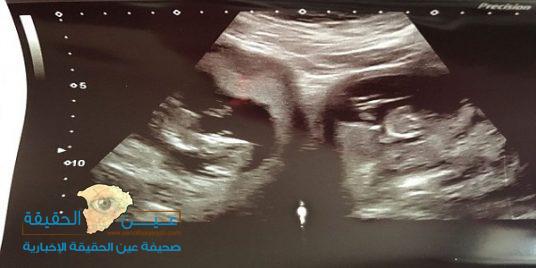

يُعد الحمل بتوأم أمرًا شائعًا وعاديًا، ولكن بالنسبة لجينيفر آشوود، فقد تسبب حملها بصدمة وحيرة كبيرة للأطباء؛ حين اكتشفوا أنها تمتلك رحمين، وحملت في كليهما بنفس الوقت.

وكشفت صحيفة “ديلي ميل” البريطانية، أن حالة جينيفر آشوود (31 عامًا)، تُعرف باسم “رحم ثنائي القرن”، حيث يحتوي بطن الأم على رحمين منفصلين.

وعلى الرغم من إنجابها سابقًا طفلتها ميلي البالغة من العمر الآن 8 أعوام، إلا أنها لم تعلم بحالتها النادرة، ولم تكتشف امتلاكها لرحمين سوى أثناء الفحص بالسونار، في الأسبوع الـ 20 من حملها الأخير.

يذكر أن جينيفر آشوود، دخلت بالمخاض في الأسبوع الـ34، وأنجبت ولدًا يدعى بيران بوزن 2.5 كغم، وطفلة تدعى بوبي بوزن 2.35 كغم، بالولادة القيصرية.